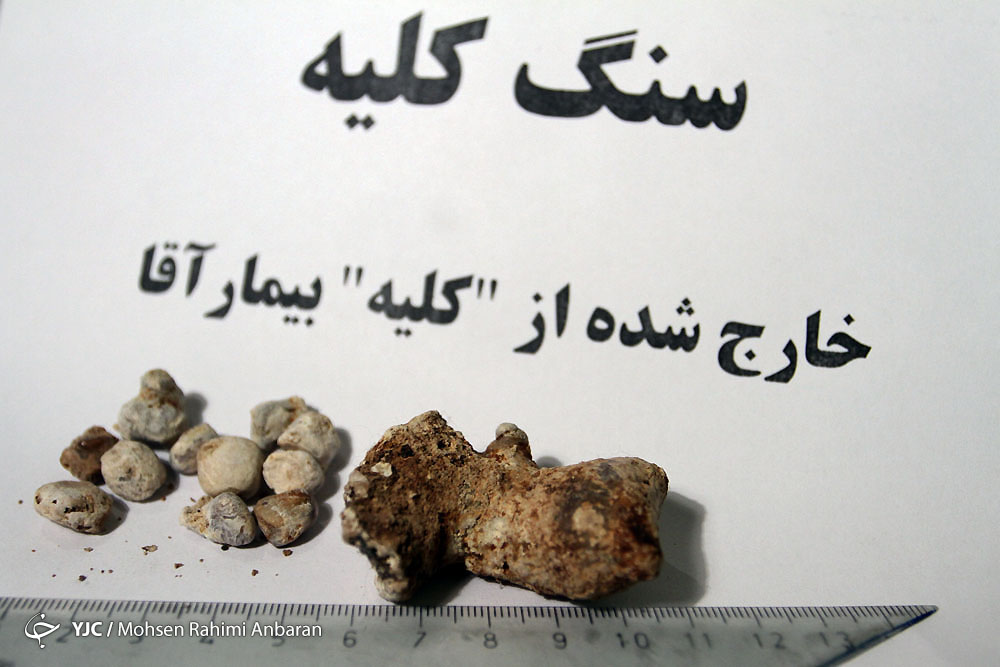

وظایف کلیه ها در بدن. و دخالت این چهار مایع را در کلیه حالات بدنی. شکل زیر عکس واقعی کلیه انسان را نشان می دهد. اگر عملکرد آن ها کم شود نیاز به دیالیز پیدا می کنند.

در هر ساعت کلیه های بدن انسان حدود ۷ لیتر مایع را از خون جدا می کنند این مایع را تصفیه کرده و مواد مفید و سودمند آن را به خون بازمی گردانند و مواد مضر آن را از راه میزنای به مثانه می فرستد تا دفع شوند. کجای بدنتان درد می کند مراجعه کنید آیا کلیه تان درد می کند درد کلیه در اثر عفونت کلیه یا آسیب رسیدن به آن ایجاد می شود. اما کار و وظیفه کلیه ها در بدن چیست بیا یاد بگیریم. زمانیکه کلیه ها بدرستی فعالیت کنند مواد زائد از بدن داخل ادرار ترشح می شوند همچنین کلیه ها در تنظیم سایر مواد معدنی در بدن مانند.